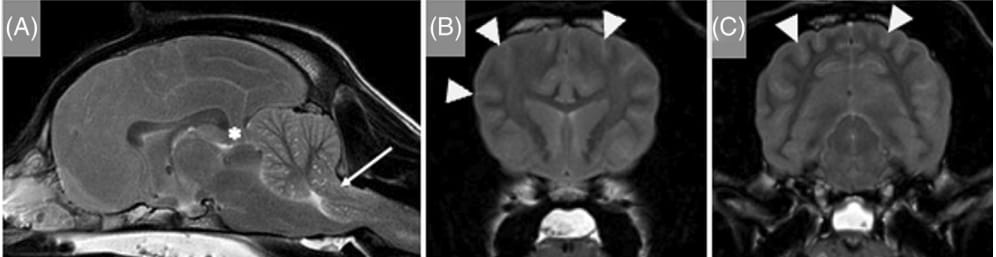

Magnetic resonance images of the head of a 2.5-year-old intact male spaniel crossbreed dog that presented after cardiopulmonary

arrest and successful resuscitation at the referring veterinary surgeon's hospital. T2-weighted sagittal (A) and transverse images at the level of the

head of the caudate nuclei (B) and rostral colliculi (C) show a diffusely swollen brain with almost complete obliteration of the cerebral sulci

(arrowheads) and ventricular compression. There is diffuse bilateral subtle to moderate loss of gray and white matter differentiation. These

changes are more severe dorsally within the parietal and occipital lobes. There is caudal transtentorial herniation (asterisk) with compression and

caudal displacement of the rostral cerebellum. Additionally, the cerebellum is protruding into the foramen magnum (arrow) with severe

compression of the underlying medulla oblongata. The cervical spinal cord is swollen with obliteration of the surrounding cerebrospinal fluid

signal. The caudal aspect of the nasal cavity, nasopharynx, caudal aspect of the oral cavity and frontal sinuses contains T2W hyperintense

material (likely compatible with regurgitation of gastric contents). Hyperintensities are reported relative to normal gray matter.